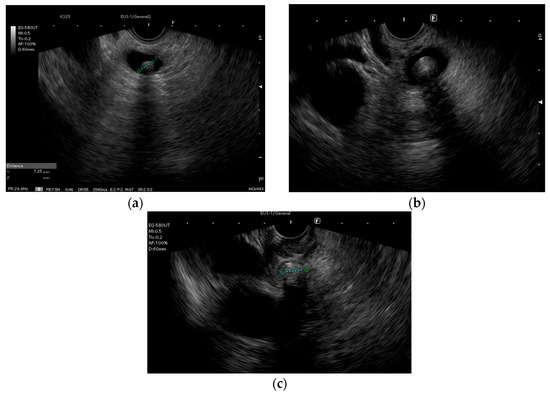

Figure 1